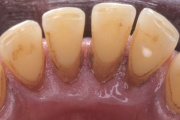

- igemepiir on taandunud (3)

- hamba kinnitussidemete kadu (3)

- igemepealne hambakivi (5)

- igemealune hambakivi (4)